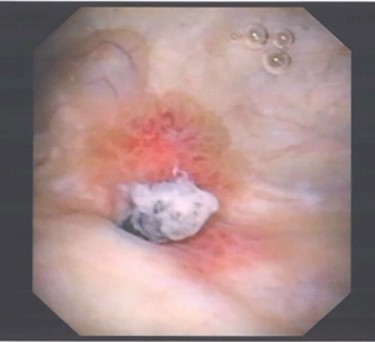

Mid-stream urine culture was negative. Flexible cystoscopy identified a 1 cm raised abnormal lesion on the right postero-lateral wall, suspicious for malignancy (Fig. 1).

Image of suspected ‘tumour’ on right posterolateral wall of the bladder, taken during flexible cystoscopy.